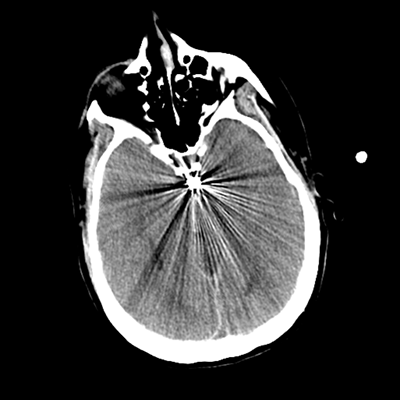

The patient goes down to CT. The following images are obtained. The subdural fluid collection is stable, as is the ventricular caliber.

Starting with the non-contrast head CT, we can appreciate that there's actually not much residual subarachnoid blood at all; it's essentially all resorbed already (and cleared through the EVD). The ventricular caliber is stable. With the CTA head (for convenience's sake, the MIPs were shown), it's subtle, but we can see that the PCAs on each side are not as smooth and regular. The right MCA, starting at the bifurcation, also becomes narrower. This is [radiographic] vasospasm. Now, looking at the CT perfusion-- specifically, the Tmax (MTT) map that were selected-- there's clearly some abnormality within the bilateral cerebellar hemispheres and occipital lobes. Not a lot, but it's there. Delving further into this map, we can appreciate that the areas of abnormality are mainly green, signifying that these areas have Tmax > 6 seconds. This is the threshold that is specific, not sensitive, for vasospasm.

Putting this all together, we have thus identified radiographic vasospasm with the vessel imaging, with perfusion abnormalities that are concordant with it. Does the area of vasospasm and hypoperfusion correlate with the patient's clinical exam?

Yes! It does. The patient had a decline in level of consciousness with diffuse loss of motor function. This does correlate to the basilar territory. (Alternatively, bilateral MCA vasospasm could also be responsible, reminding us that a decline in consciousness could technically be focal/multifocal.) Thus, we can say that this patient does have clinical vasospasm. Whether this will develop into irreversible DCI remains to be seen; at least, the non-contrast head CT and the other portions of the CT perfusion (not shown) currently don't [yet] suggest infarction.